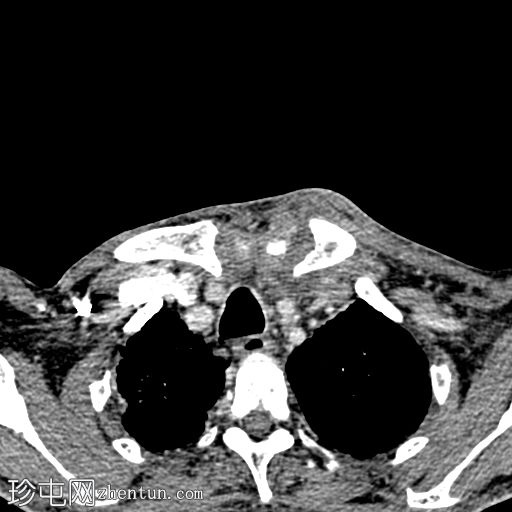

CT

轴位

平扫

轴位增强扫描

动脉期

CT显示胸锁关节周围强化的积液,伴邻近软组织炎症和锁骨内侧骨侵蚀,符合化脓性关节炎和脓肿的

影像

学表现。

病例讨论

影像学特征符合非糖尿病患者的胸锁关节化脓性关节炎。